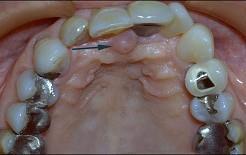

问题 无牙颌患者的口内特征为 ( )

选项 A.牙列缺失 B.牙冠缺损 C.牙体缺失 D.牙列缺损 E.牙体缺损

答案 A